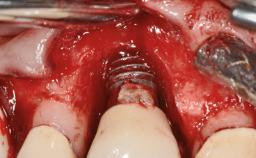

Peripheral Giant-cell Granuloma Associated with Peri-implant Tissues

# of Implants 5

Type of Implants One-Piece